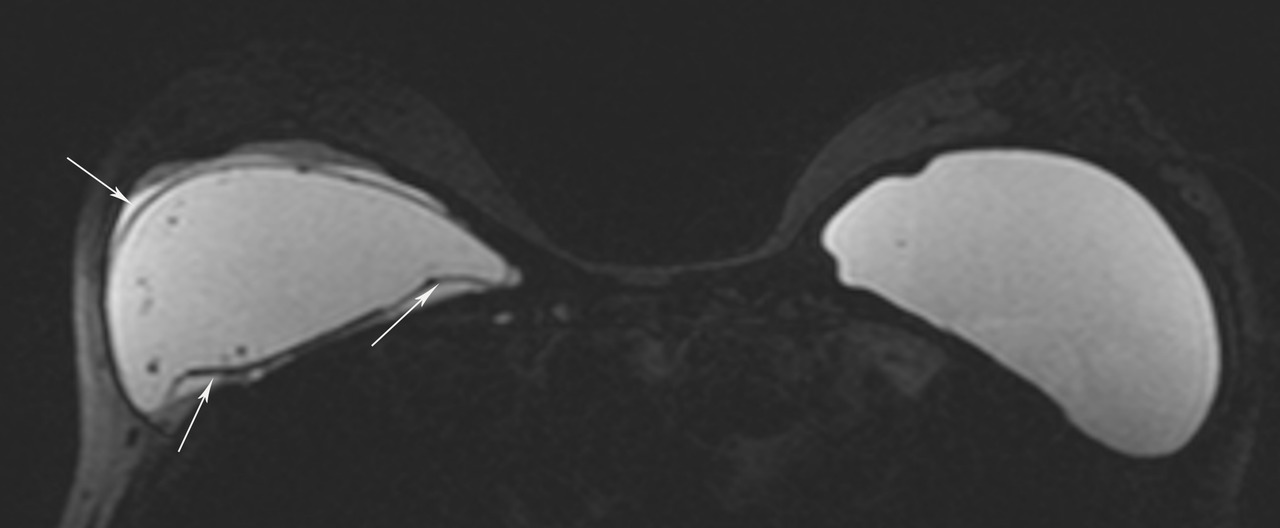

• extracapsulaire (fig. 3 et 4), contenu hétérogène avec échos internes et perte du contour régulier de la paroi à l’échographie. Diagnostic confirmé par l’IRM mammaire avec séquences dédiées silicone, qui montre l’incontinence de la prothèse (paroi irrégulière) et des dépôts de silicone rétro- ou périprothétiques. Des ganglions chargés en silicone peuvent être visibles.